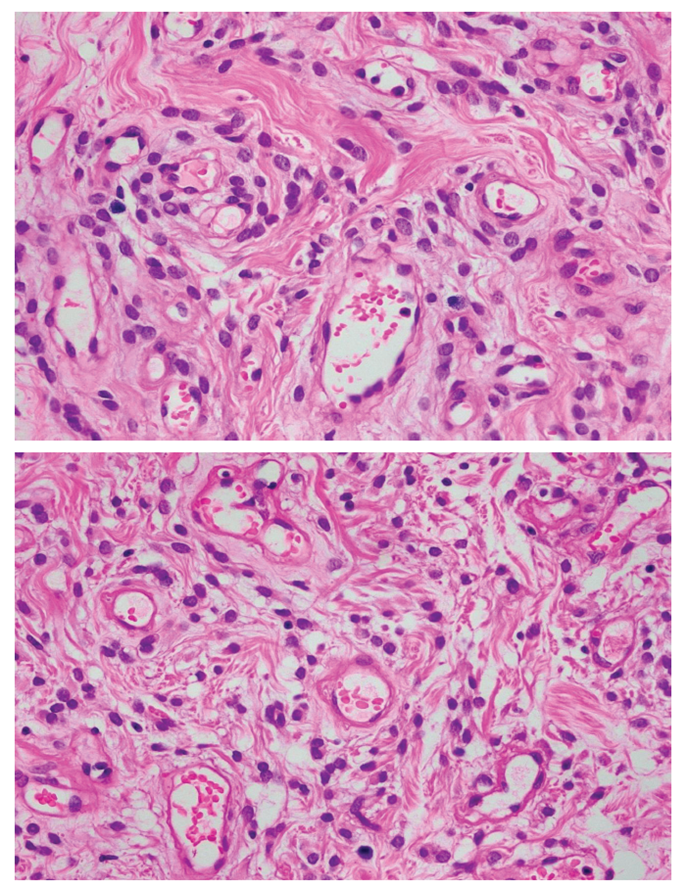

SMARCB1 (INI-1)-deficient Sinonasal Carcinoma

A Case Report and its Clinical Implications on Diagnosis and Management

Dianne Mae Tan, Glezette Anne Altares, Rose Lou Marie Agbay, Jose Carnate Jr.

Lipomatous Angiomyofibroblastoma in the Vulva

A Case Report with Review of Literature

Clarisse Young, Agustina Abelardo